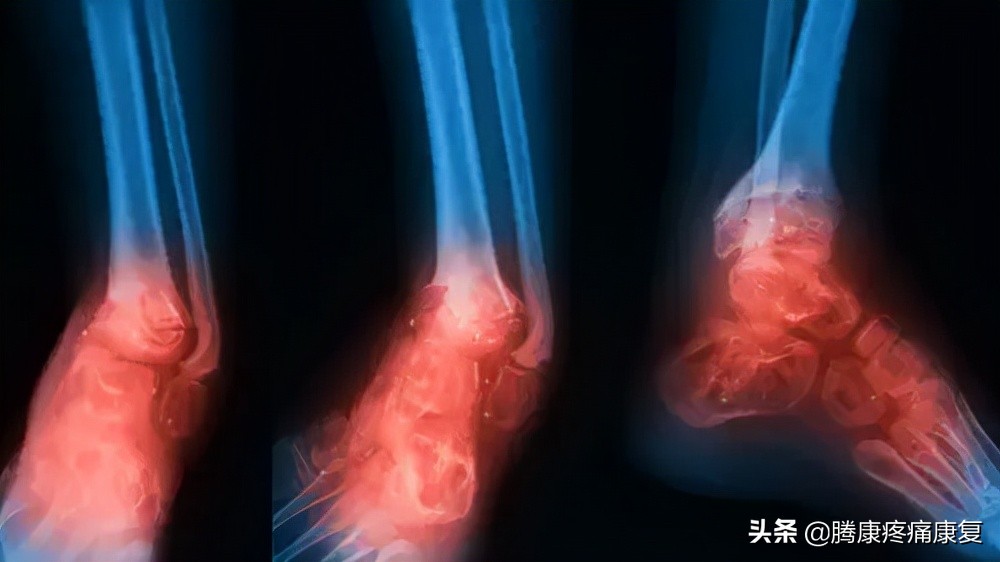

小腿骨折

小腿的胫骨或腓骨骨折可能是由于摔倒或腿部外伤性打击(如车祸)引起的。

这种损伤可能导致严重的小腿疼痛,肿胀,行走困难或无法承受任何重量。

小腿疼痛可由肌肉、骨骼、神经或肌腱的损伤以及感染或血液流动受到影响的状况引起。医生可以通过影像学检查或血液检查来诊断疼痛。